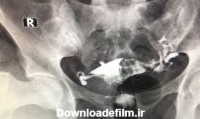

عکس رنگی رحم یا هیستروسالپنگوگرافی یکی از روش های تشخیصی شیوه ی تصویربرداری با اشعه ایکس است که معمولاً برای بررسی آناتومی رحم و لوله ها انجام میشود. عکس رحم

عکس رنگی رحم یا هیستروسالپنگوگرافی نوعی روش تصویر برداری یا رادیوگرافی برای مشاهده رحم و لوله ها است که به وسیله نوعی اشعه ایکس به نام فلوروسکوپی و یک

عکس رنگی رحم برای تشخیص علت ناباروری، بررسی لوله های فالوپ پس از عمل جراحی لوله ای یا پیوند مجدد لوله ای انجام می شود تا از بسته بودن لوله ها اطمینان حاصل شود.